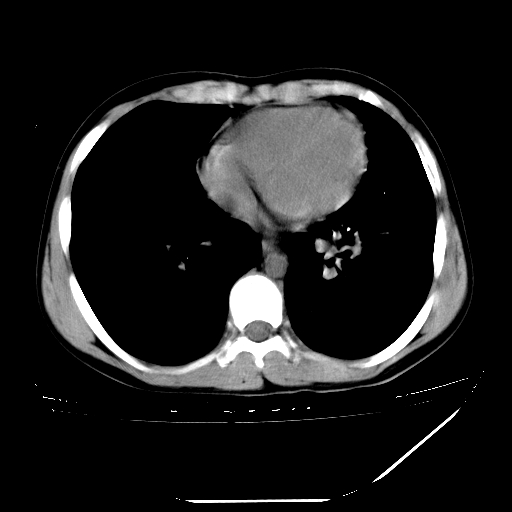

男,13岁,咳嗽、咳痰伴发热一周。

中上纵隔见多枚淋巴结肿大,部分相互融合成团片,左肺门增大,上叶支气管变窄,肺内多处斑片状 索条状及棉絮状致密影。临床“男,13岁,咳嗽、咳痰伴发热一周。”首先考虑:原发综合征!不除外淋巴瘤可能!

中上纵隔见多枚淋巴结肿大,部分相互融合成团片,左肺门增大,上叶支气管变窄,左肺支气管血管束增粗,可见磨玻璃样影。临床“男,13岁,咳嗽、咳痰伴发热一周。”首先考虑:淋巴瘤可能性大!

中上纵隔见多枚淋巴结肿大,部分相互融合成团片,纵隔内脂肪间隙模糊,左肺门增大,上叶支气管变窄,左肺支气管血管束增粗,可见磨玻璃样影。考虑纵隔淋巴管炎